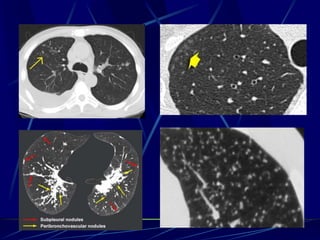

Langerhans Cell Histiocytosis

HRCT Findings

Small peribronchiolar nodules (1-5mm)

Thin-walled cysts (< 1cm),

Bizarre and confluent

Ground glass opacities

Late signs: irreversible / parenchymal fibrosis

Honey comb lung, septal thickening, bronchiectasis

Key Features

Upper lobe predominance

Combination of cysts and noduli

Characteristic stages

Increased Lung volume

Sparing of costophrenic angle